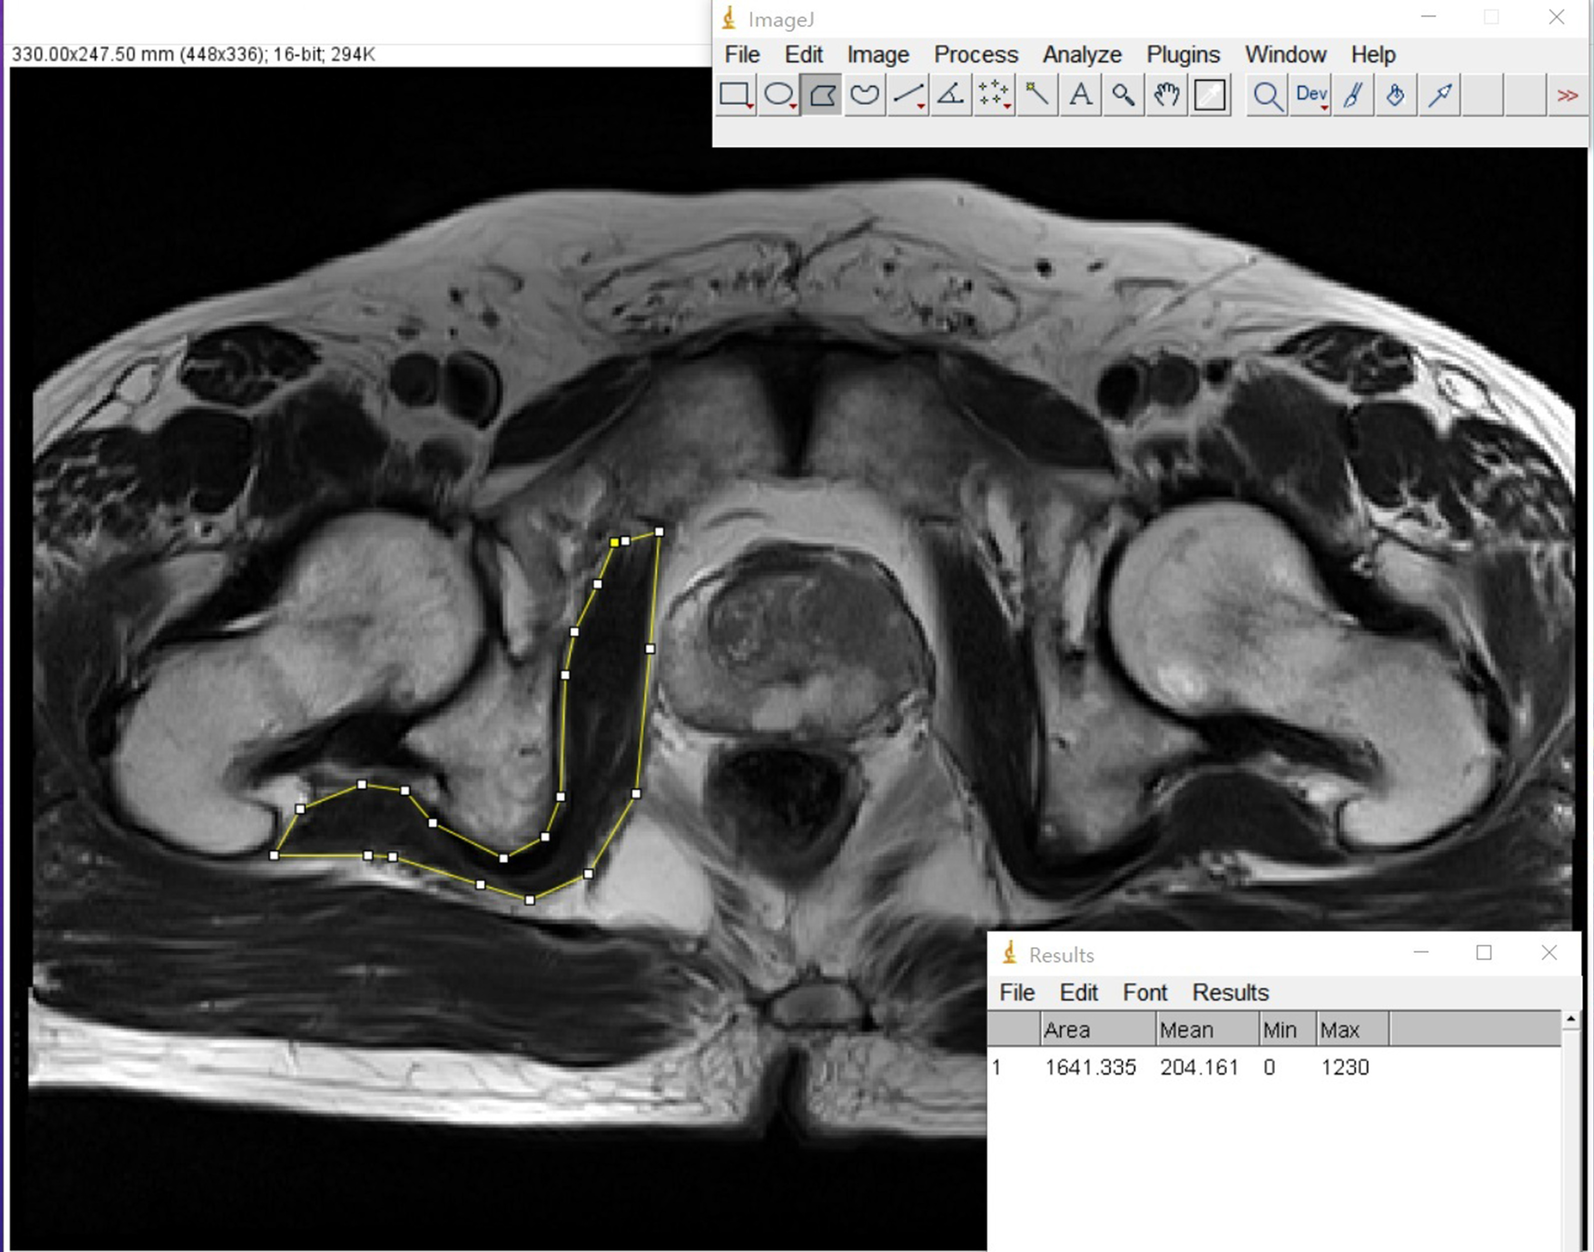

Fig. 1From: Effect of pre-operative internal obturator muscle mass index in MRI on biochemical recurrence of prostate cancer patients after radical prostatectomy: a multi-center studyThe measuring methods of internal obturator muscle width in the pelvis MRI for IOM mass indexBack to article page